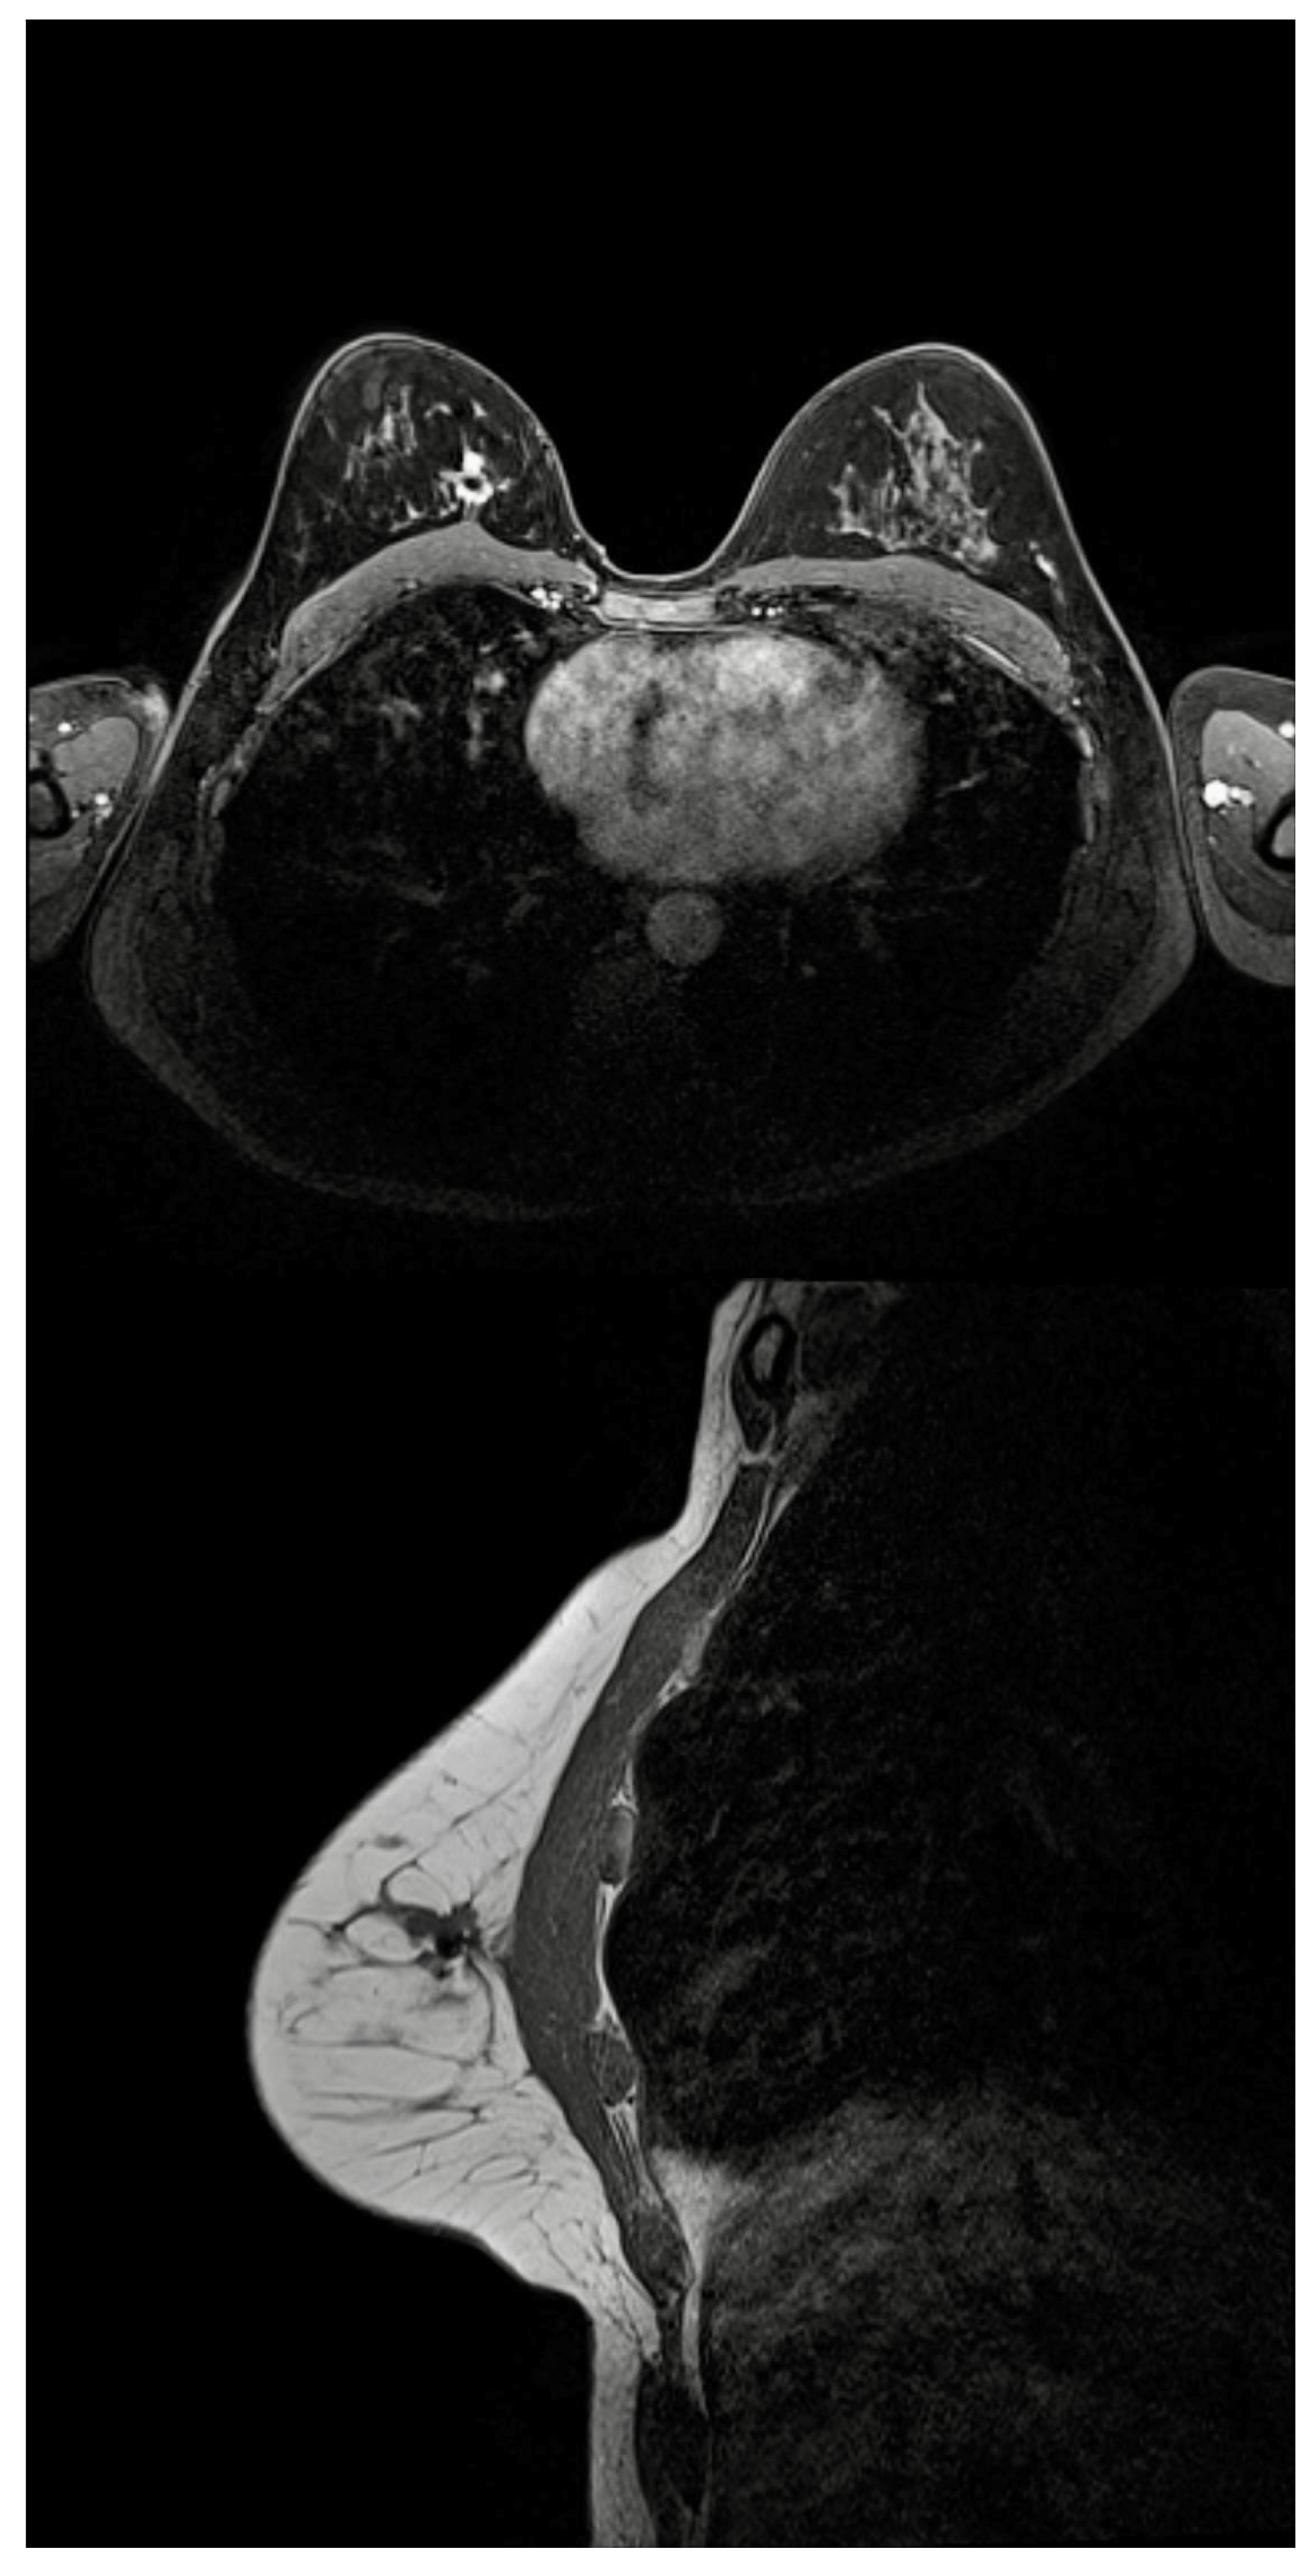

- Tayeh, S.; Muktar, S.; Heeney, J.; Michell, M.J.; Perry, N.; Suaris, T.; Evans, D.; Malhotra, A.; Mokbel, K. Reflector-guided localization of non-palpable breast lesions: The first reported european evaluation of the savi scout(r) system. Anticancer Res. 2020, 40, 3915–3924. [Google Scholar] [CrossRef] [PubMed]